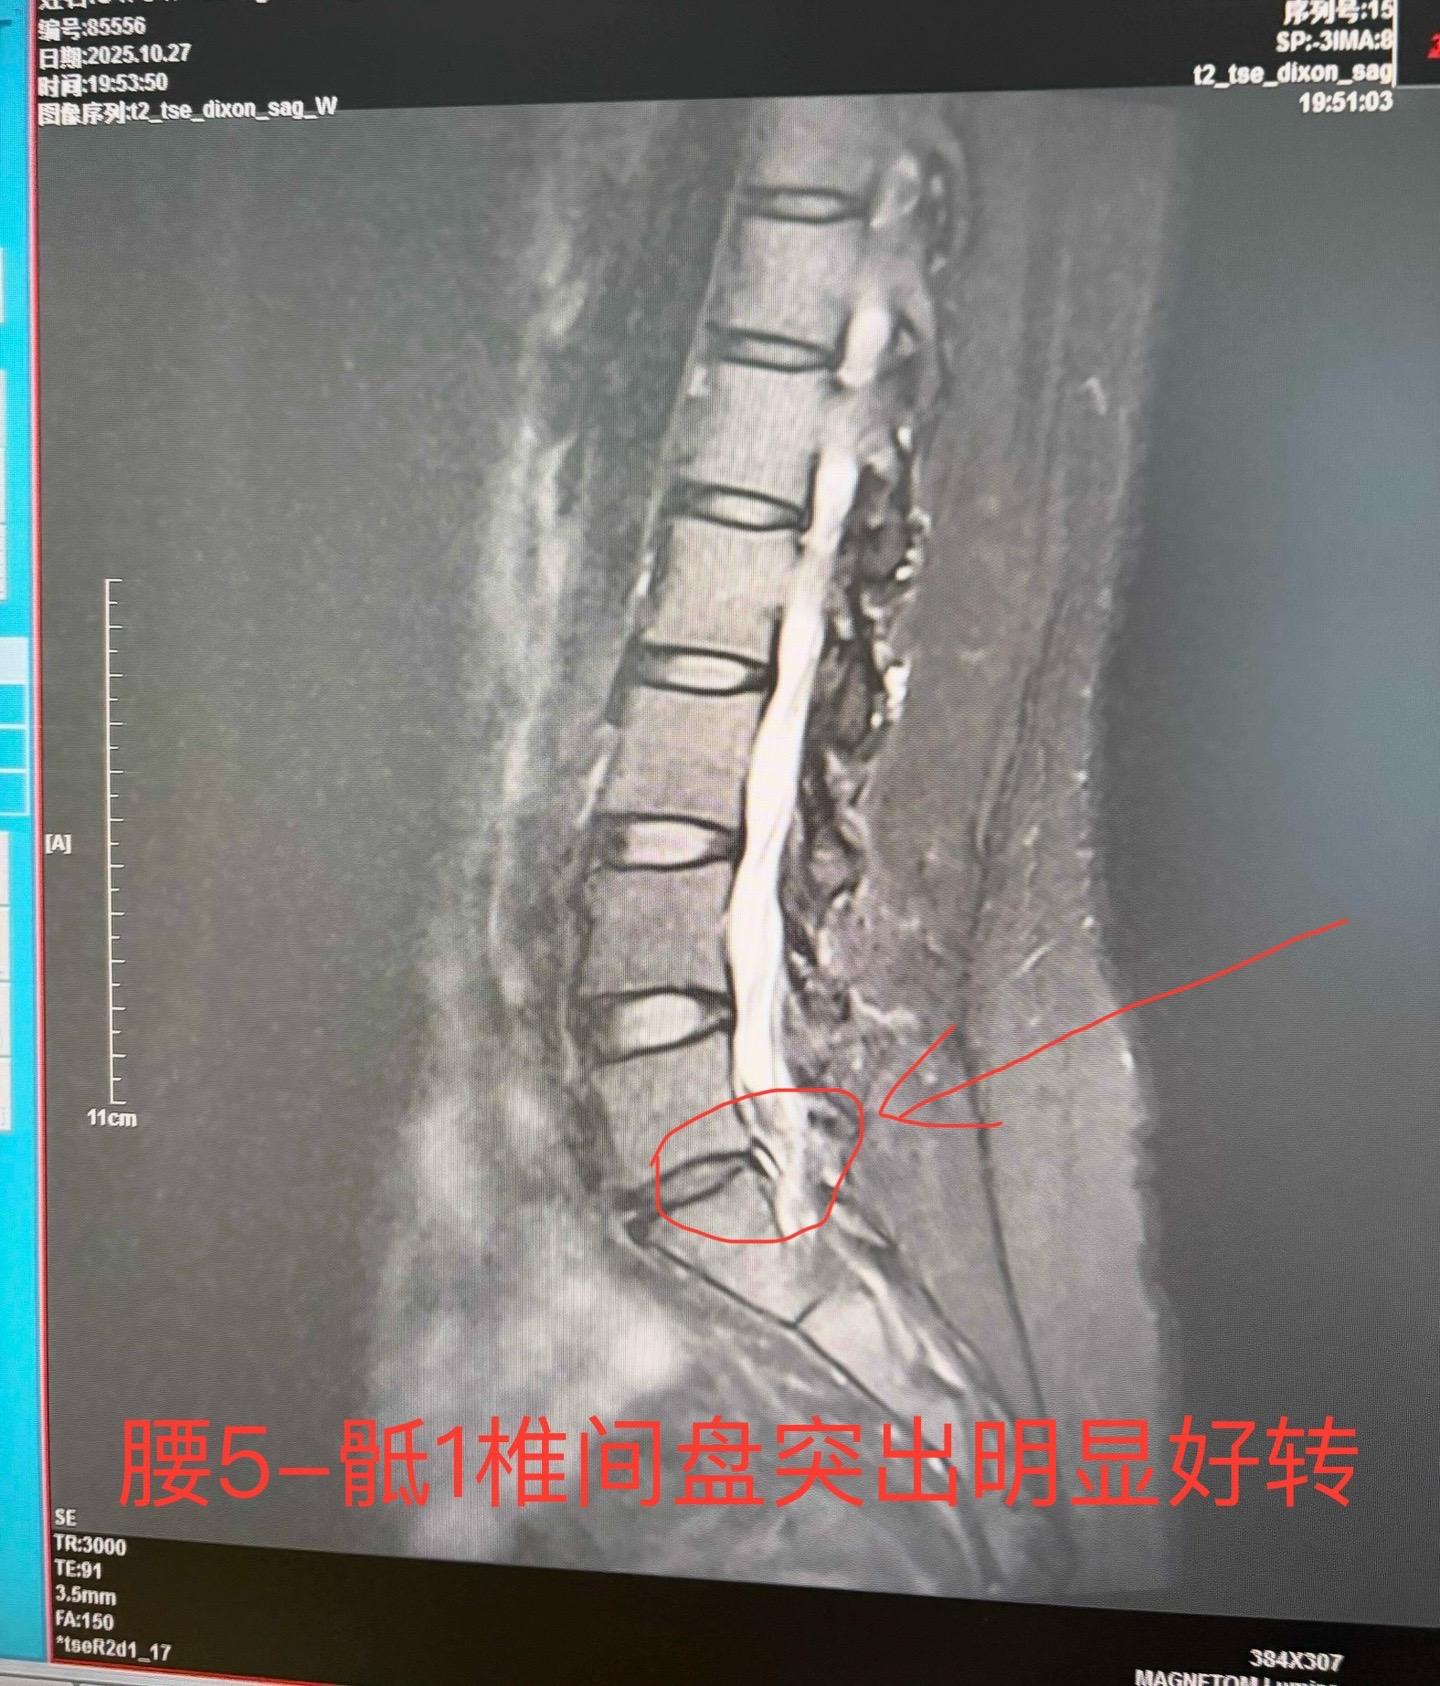

椎间盘脱出了能不能保守治疗?今天碰到一个病例,四年前椎间盘脱出,选择保守治疗,四年后复查,椎间盘脱出已经基本消失。这类病例还是比较少见,每个病人的身体类型都不一样,治疗也不一样。